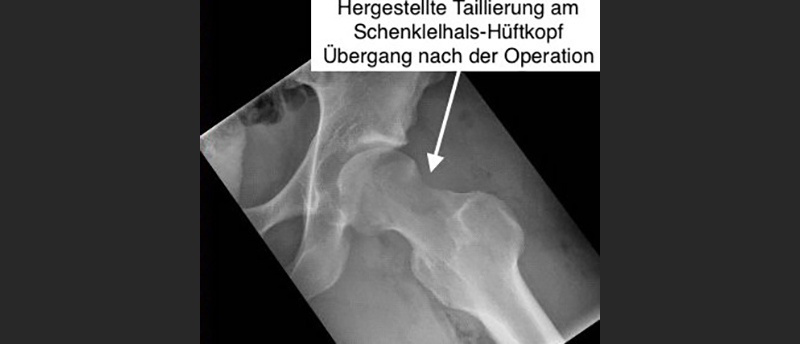

Die Knochenüberschüsse am Gelenkpfannenrand oder Schenkelhals werden mit einer 5 mm grossen Fräse nach MRI-Planung abgeschliffen. Der Hüftkopf muss zum Schluss auch zum Schenkelhals hin dreidimensional abgerundet sein. Ist die Gelenklippe gerissen, wird sie genäht oder ersetzt.